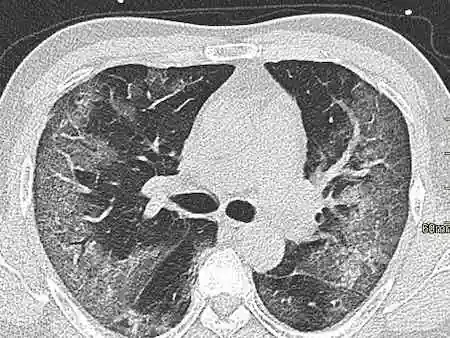

新冠肺炎患者肺功能不可恢复

病毒性肺炎影像学特征

总结新型冠状病毒肺炎的影像学特征│以影识病

新型冠状病毒感染肺炎的影像学特点_病毒性肺炎_病毒性肺炎检查 - 好

新冠医学影像合集!

不同时期及特殊人群新冠肺炎影像学表现看指南怎么说│指南共识